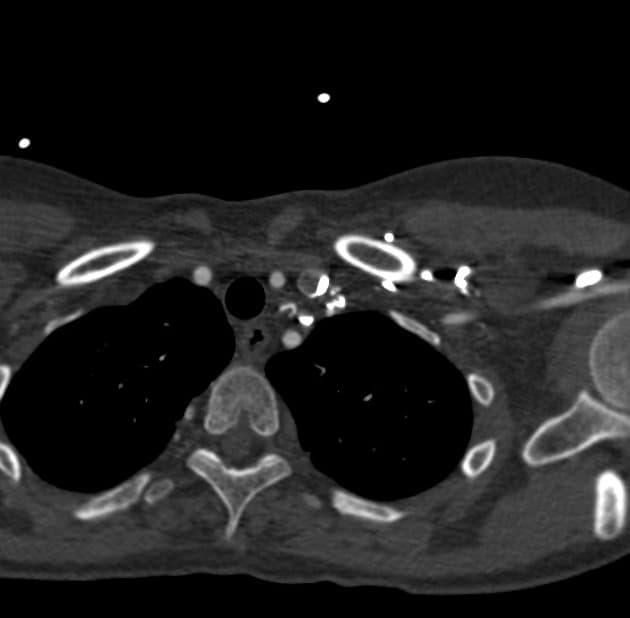

Axial C+ arterial phase

Bệnh tim bẩm sinh phức tạp: chuyển vị đại động mạch có sửa chữa bẩm sinh kiểu L, thất trái nhỏ, hội chứng thiểu sản tim trái (HLHS) - thiểu sản cung động mạch chủ. Tình trạng sau phẫu thuật nối tĩnh mạch chủ - động mạch phổi toàn phần (TCPC) và đặt stent vị trí nối TCPC - động mạch phổi trái (LPA).

BÀN LUẬN: Một ví dụ về tuần hoàn Fontan ở một bệnh nhân có miệng nối Damus-Kaye-Stansel do bệnh tim bẩm sinh phức tạp kèm chuyển vị đại động mạch kiểu L (L-TGA) và hội chứng thiểu sản tim trái (HLHS).

Việc tiêm đồng thời thuốc cản quang chứa iod bằng cách lựa chọn vị trí tiêm phù hợp (qua chi trên và chi dưới) hoặc phương pháp quy trình tiêm kép giúp đảm bảo thời điểm bơm thuốc và bắt đầu quét, cho phép toàn bộ vòng tuần hoàn Fontan ngấm thuốc đậm hơn, từ đó tối ưu hóa và làm đồng nhất sự tăng quang đồng thời của đường dẫn Fontan và các động mạch phổi.

Sự chênh lệch thời gian ngấm thuốc của tĩnh mạch chủ trên (SVC) và tĩnh mạch chủ dưới (IVC), sự hòa trộn không hoàn toàn trong vòng tuần hoàn Fontan, và dòng chảy thuốc cản quang khác biệt vào các động mạch phổi dẫn đến tình trạng ngấm thuốc không đồng nhất của đường dẫn Fontan.

Những khó khăn trong việc làm hiện hình cả động mạch phổi và động mạch chủ trong cùng một thì trong bối cảnh kết nối tĩnh mạch chủ - phổi toàn phần (TCPC) bao gồm khả năng xuất hiện nhiễu ảnh dòng xoáy, dòng tĩnh mạch gan chưa ngấm thuốc, hoặc sự hòa trộn không hoàn toàn. Một lựa chọn khác là quét thì muộn khi máu tĩnh mạch trở lại đường dẫn Fontan sau khi đi qua tuần hoàn hệ thống.